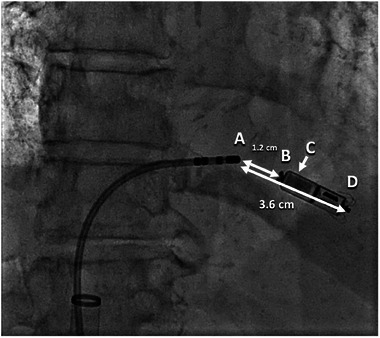

Methods: We conducted a single-center, retrospective case series of patients who underwent concurrent Micra implantation and radiofrequency (RF) AVN ablation from January 2019 to May 2023. A simulated computer model was created to characterize the interaction between the dissipated power at the Micra cathodal electrode as a function of the distance between the RF ablation catheter and the location of the return electrode.

Results: Fifteen patients were included. Most were elderly, White, female, and had persistent AF. One had transient, acute loss of ventricular capture that resulted in asystole and required emergent pacing from the ablation catheter. A proposed strategy of moving the RF return electrode to a cranial position from a caudal position was shown by computer modeling to direct more RF current away from the Micra and lower the dissipated power at the Micra cathodal electrode.